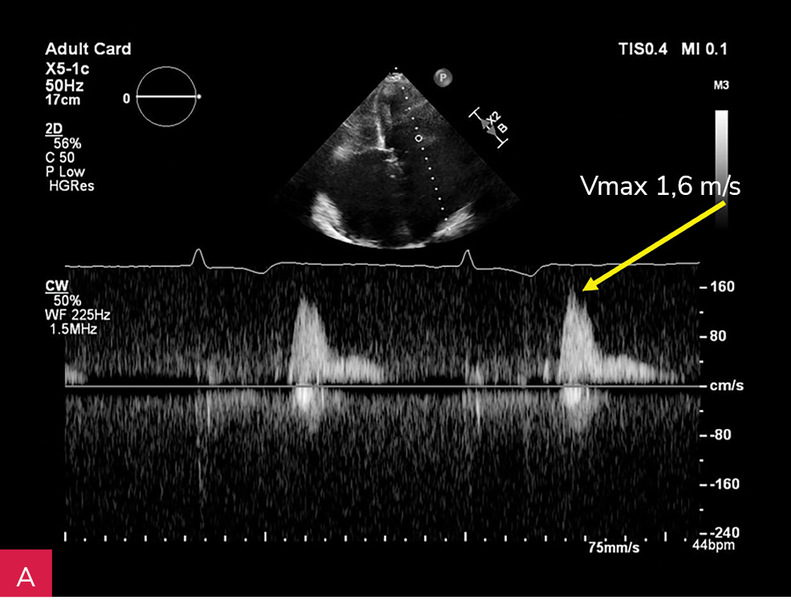

Rycina 2A, B. Zmiana u podstawy tylnego płatka mitralnego, obejmująca jego nasadę, a także fragment mięśnia ściany dolno-bocznej lewej komory w projekcji przymostkowej w osi długiej LAX (A) oraz w projekcji zmodyfikowanej, w której lepiej uwidoczniono hiperechogeniczną uwapnioną otoczkę zmiany oraz powodowany przez nią cień akustyczny (B)